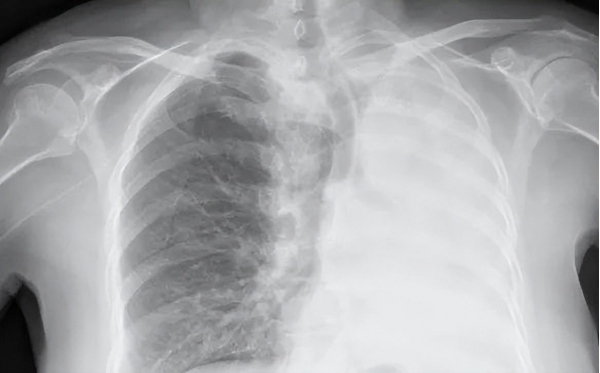

20岁小伙发烧2天以为是小感冒,想硬扛却被送重症监护室,医生:肺部大面积"变白"

近日,20岁小伙患上流感,以为是小感冒,硬扛2天,却被送重症监护室。经CT检查,因肺部感染多种病毒,肺大面积"变白"了。

"白肺"是一个口语化描述,用于描述重症肺炎患者在X光或CT检查下的表现,即患者的肺部显影呈大片白色区域。重症肺炎患者肺部存在大量炎性渗出物,导致肺部在影像学上显示白色区域。一般而言,当白色影像区域面积达到70%到80%时,才会被称为"白肺"。重症肺炎患者可能会出现缺氧、胸闷气短、呼吸不畅、乏力等症状。

"白肺"并非一个专业医学术语,而是一个非正式的描述,在医学影像上更准确的表达可能是"弥漫性阴影"或"肺实变"。此外,影像结果只是临床判断和治疗的一部分,医生还会根据病史、体格检查结果和实验室测试来做出诊断。